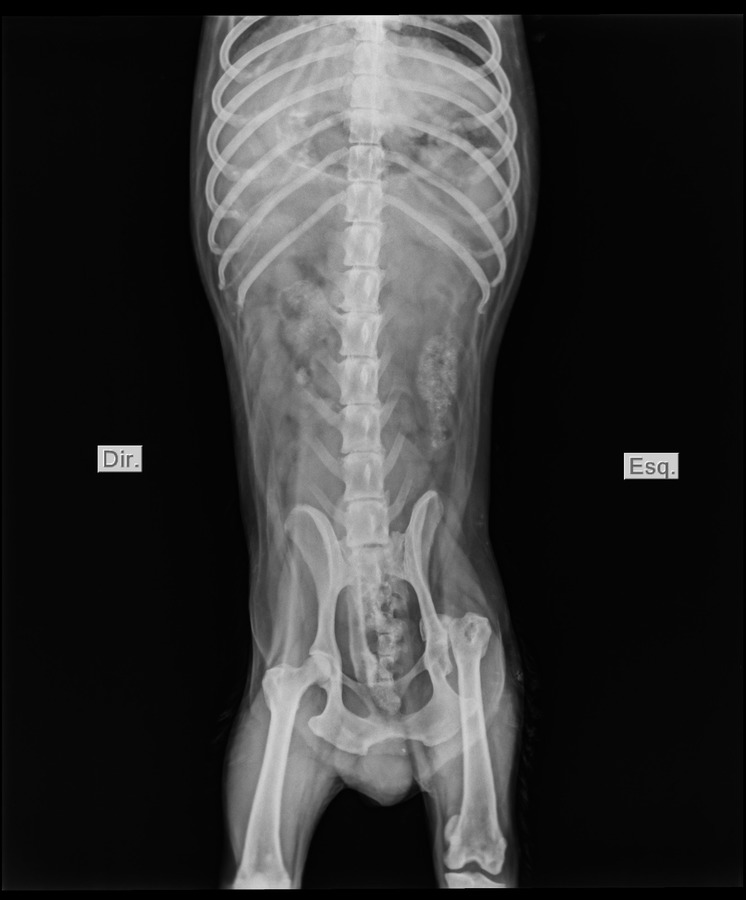

Além de ferimento severo na região do ânus, exames de Raio X mostraram que o animal também apresentava deslocamento em uma das pernas, mais precisamente, na região da cabeça do fêmur.